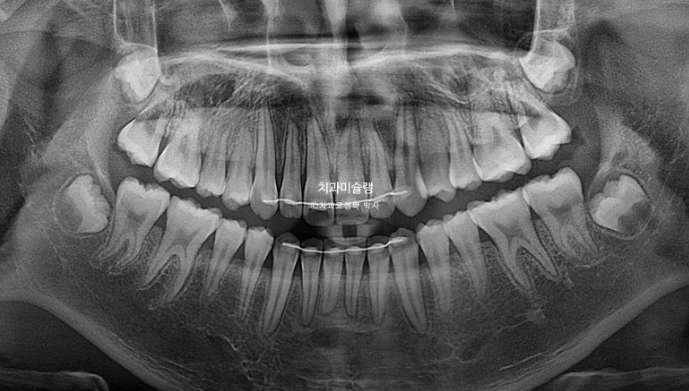

유치가 위 아래 합쳐서 아직 5개가 남아있어 인비절라인 퍼스트 어린이 교정 권유드렸습니다.

다행히 남아있는 유치 사이즈가 나중에 나올 영구치 사이조보다 크고 여러가지를 계산해보면 따로 영구치 발치 없이도 위앞니 기준 3mm 후방이동이 가능할 것으로 예상이 됩니다.

그 사이 남아있던 유치가 빠지고 영구치가 잘 나오고 있습니다.

드디어 남은 유치가 다 빠졌습니다.

그 사이 마지막 작은어금니까지 모든 영구치가 나와 교합이 완성이 되었습니다.

치료기간동안 치근흡수는 없으며 치근평행도는 좋습니다.